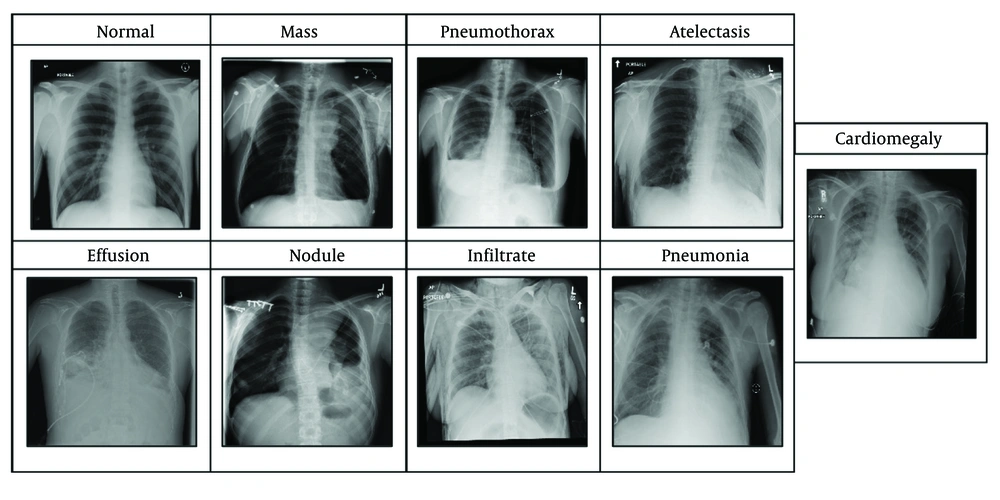

The dataset (15) includes eight lesions, namely cardiomegaly, effusion, infiltrate, mass, nodule, atelectasis, pneumonia, and pneumothorax, as illustrated in Figure 1.

Cardiomegaly can be identified by an enlarged cardiac silhouette on an X-ray. More clearly, it indicates that the heart appears larger than it usually is, may occupy more than half of the thoracic width, and enables more prominent heart border visualization. Pneumonia can be determined by the presence of dense lobar, segmental, or patchy opacities. Effusion can be identified by the presence of fluid in the pleural space; briefly, the fluid curves upward sideways on the lung edges. Infiltration is identified as increased opacity due to fluid, pus, blood, or cells within lung tissues. A nodule is a small, round opacity that is less than 3 cm in diameter, with sharp margins. A mass is larger than a nodule and has comparable properties; thus, an opacity greater than 3 cm is considered a mass. Pneumothorax is identified by the presence of air in the pleural space, causing the affected lung to appear darker and retracted from the chest wall, where the lung is collapsed. Atelectasis is determined by compensatory overinflation of the adjacent lung, and the affected area appears opaque.